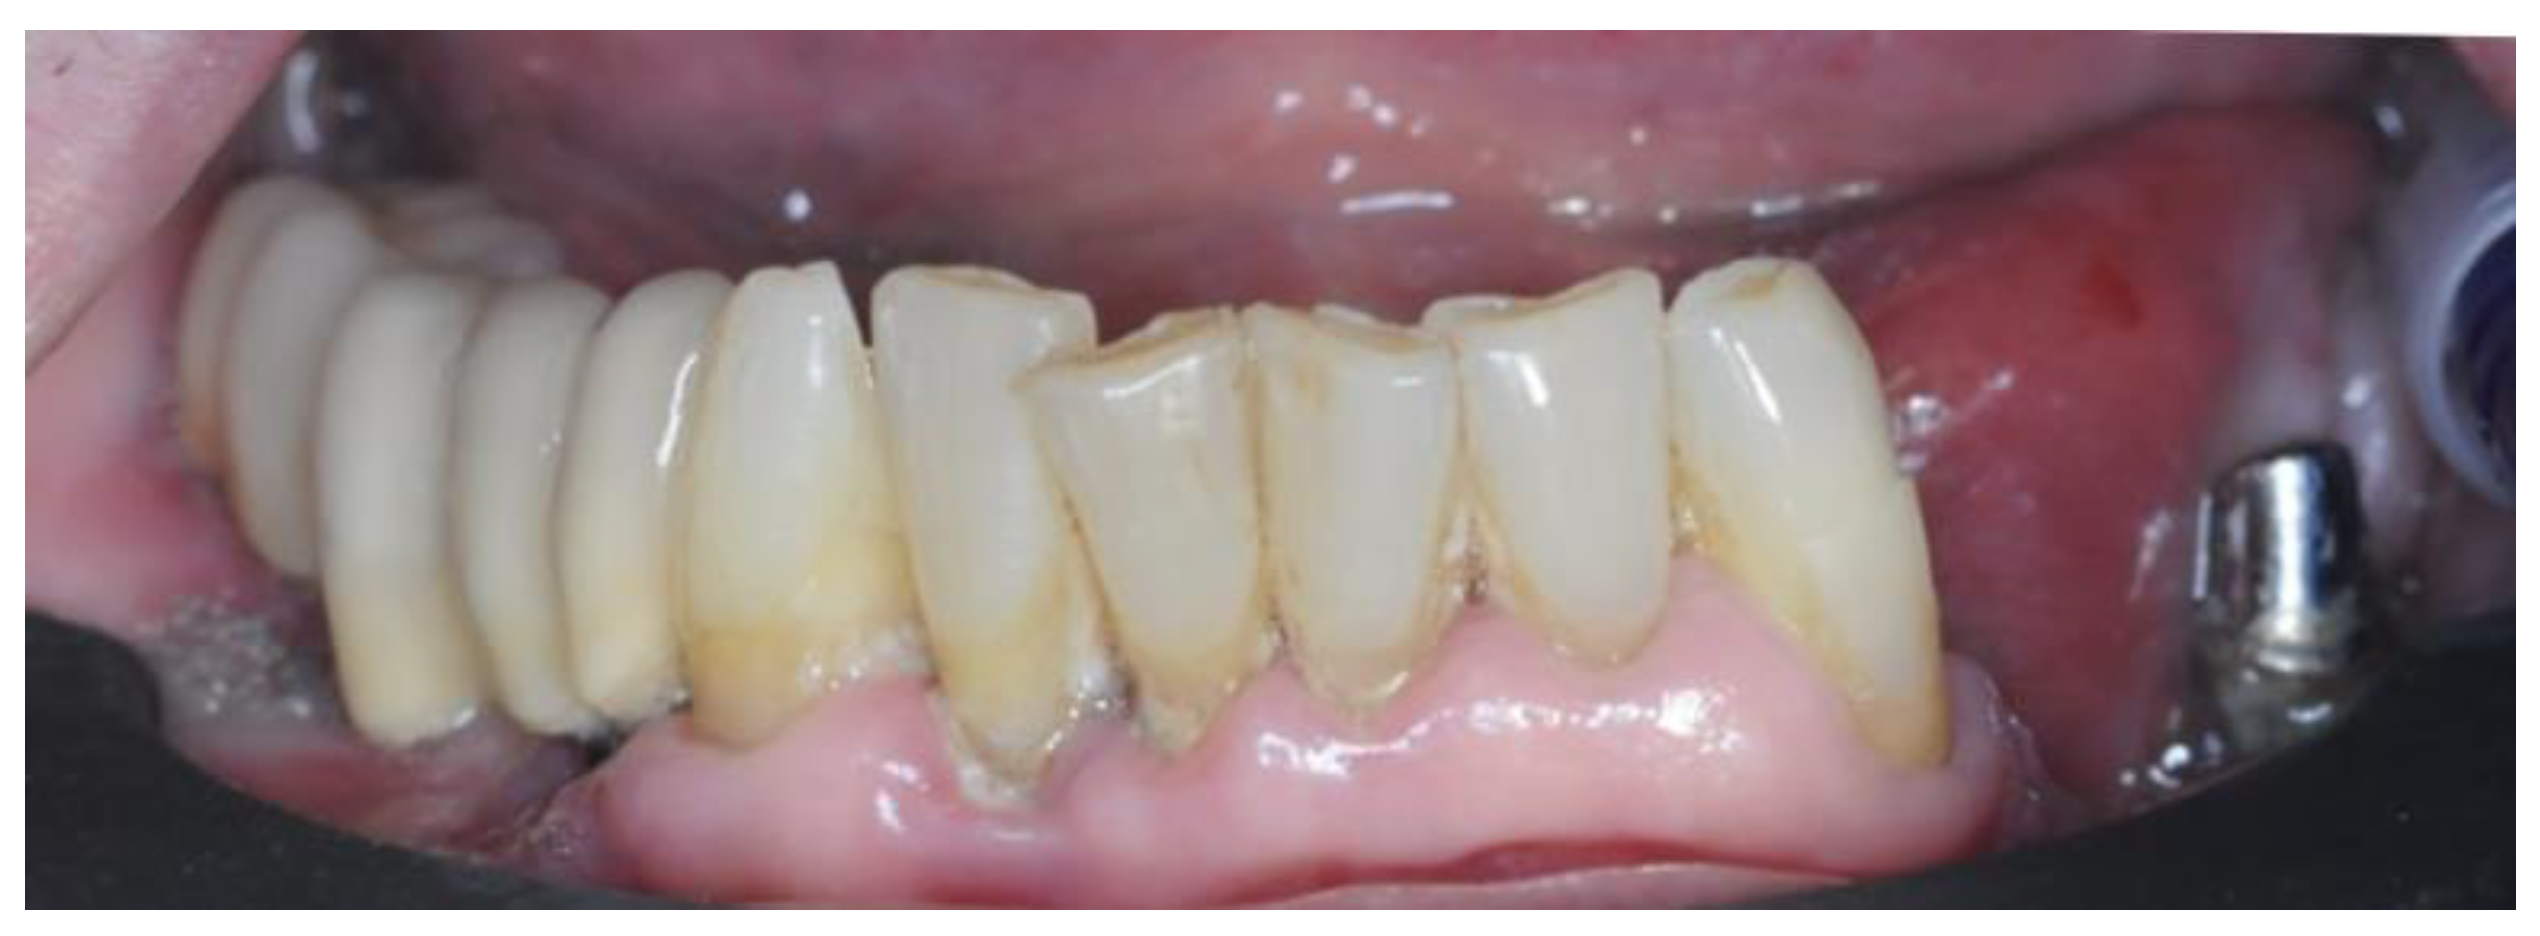

2. Materials and Methods

2.1. Planning

2.4. Surgery